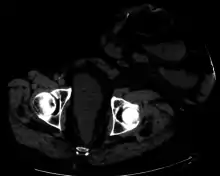

![]() Diagram showing a colostomy | |